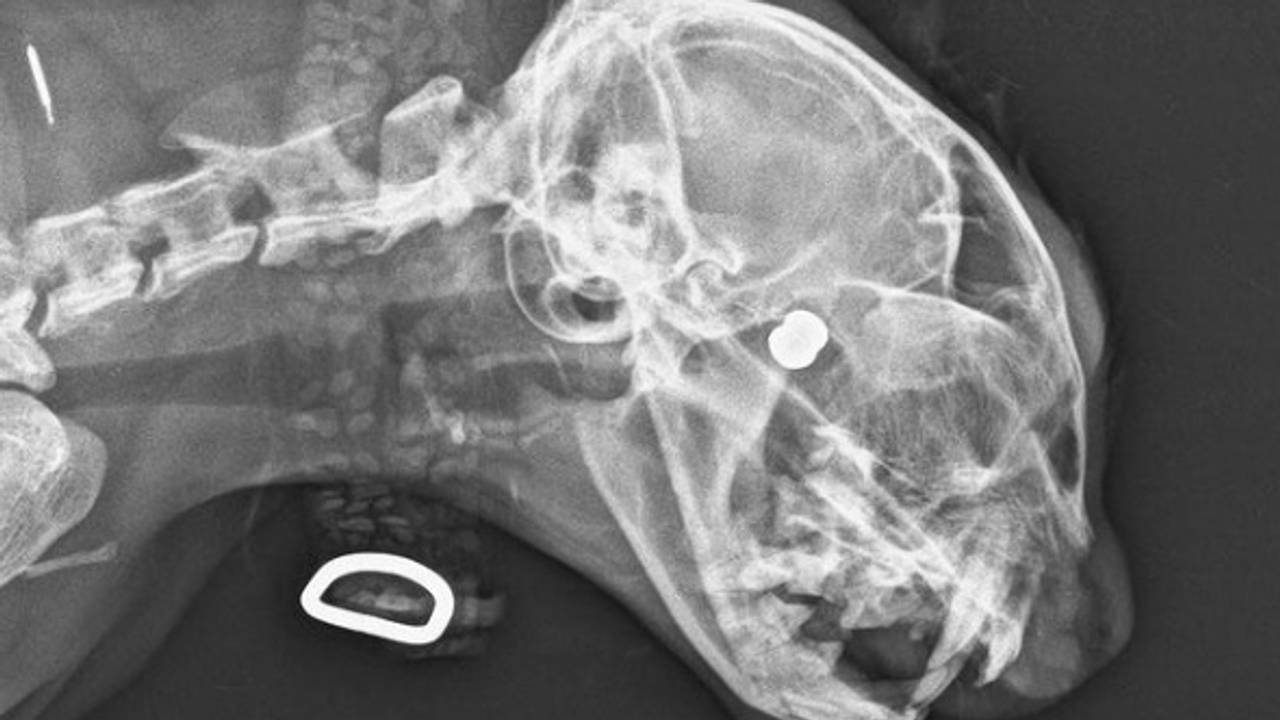

Meerdere katten zijn vorige week in de buurt van Eersel beschoten met een luchtbuks. Een van hen was er zo ernstig aan toe, dat een arts het dier moest laten inslapen. Een andere kat is in zijn oog geraakt en moet daardoor een oog missen. Dat meldt de politie op Instagram.